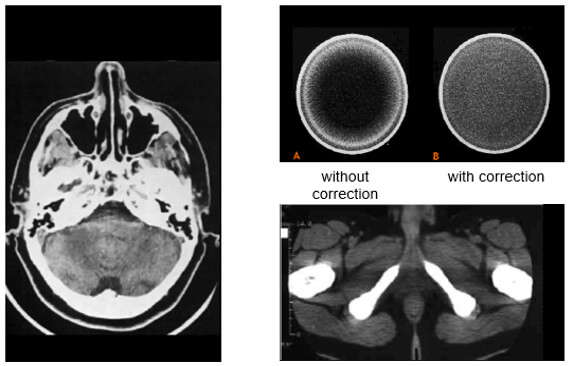

Beam Hardening Artifact

Beam hardening produces dark streaks between two high attenuation objects with surrounding bright streaks. These can be reduced by using a higher beam.

Artifacts which result from lower energy photons being absorbed, high-intensity photons are left to strike detectors.

Scanning at a higher kVp will result in a harder x-ray beam and less beam hardening artifacts.